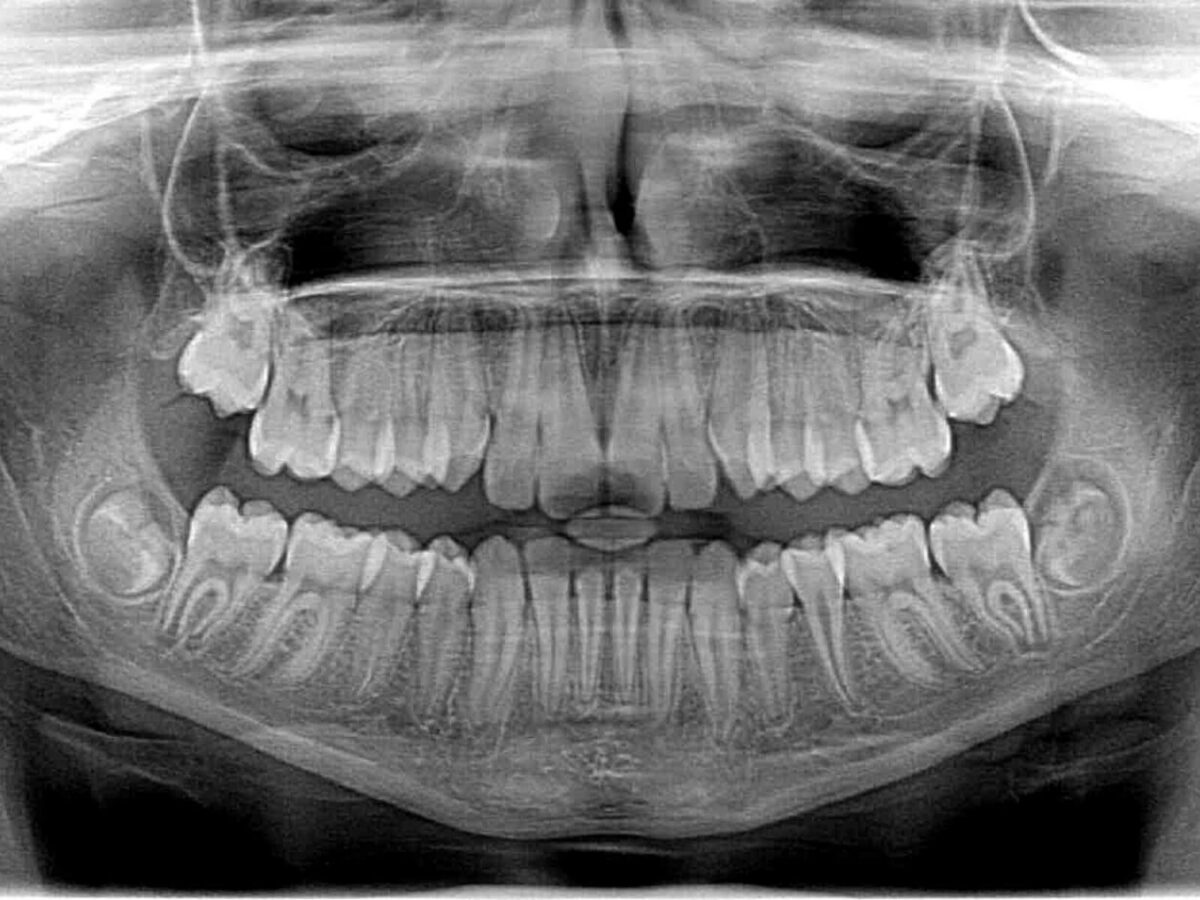

A Splendora Dentist TX explains that X-rays are more than pictures. They reveal what the eye can’t catch. A dentist checks gums, enamel, and bite by looking directly. But some issues hide. Cavities may grow between teeth. Gum disease may start under the bone. Even infections can linger quietly. Without images, these remain out of sight.

It may feel unnecessary to take X-rays when teeth look fine. But problems often hide. Cavities can grow between molars. Early gum disease can eat away bone. Infections can sit under fillings or crowns. Cysts and other unusual growths may stay hidden unless an X-ray is taken.

Dental imaging has improved greatly. Modern tools provide sharper images with less radiation. Some Splendora Dental Office TX now use digital panoramic X-rays to show the entire mouth in one image. This helps dentists see overall patterns, not just one tooth.